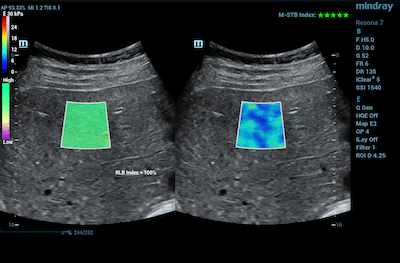

In conjunction with blood tests, shear wave elastography is used to determine the staging and progression of liver fibrosis with good sensitivity and repeatability. It is an adjunct to conventional 2D ultrasound exams, aiding in initial characterization and treatment follow-up.

Resona 7 Ultrasound SystemThe Resona 7 Ultrasound is a premium system powered by Zone sonography technology, the industry’s first virtual beamforming technology. ZST provides clear, ploppable imaging with excellent resolution and penetration. The Resona 7 offers high frame rate Sound Touch Elastography allowing for smoother transition times and faster refresh rates for more consistent acquisition and assessment during live 2D shear wave imaging. The recent addition of Ultrasound Attenuation Imaging (USAT) provides an accurate and quantifiable method of diagnosing and monitoring liver steatosis. |

Resona I9 Ultrasound SystemThe Resona I9 Ultrasound is a powerful and portable solution powered by Zone sonography technology, the industry’s first virtual beamforming technology. ZST provides clear, ploppable imaging with excellent resolution and penetration. The system is equipped with high frame rate Sound Touch Elastography allowing for smoother transition times and faster refresh rates for more consistent acquisition and assessment during live 2D shear wave imaging. |